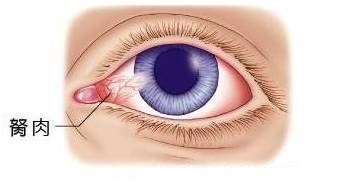

眼部胬肉 :指眼球结膜增生而突起的肉状物(wù)

胬肉長(cháng)到黑眼珠边缘上就停止了,它不充血,微红色,头部扁平,颈及體(tǐ)部较薄,处于相对静止状态,但不自行消退。 另外有(yǒu)一种假性翼状胬肉,它可(kě)以生長(cháng)在黑眼珠边缘任何一个部位,一般比较小(xiǎo),表面呈灰白色,但也有(yǒu)较肥厚的。常常由于外伤、角膜边缘溃疡、结膜的化學(xué)或热烧伤形成瘢痕组织,形成后一般不再生長(cháng)。它和前面两种翼状胬肉性质上完全不同。 形成的原因:

翼状胬肉為(wèi)球结膜及纤维血管组织呈翼状侵入角膜浅层,是一种结膜组织的增殖变性引起的病变。